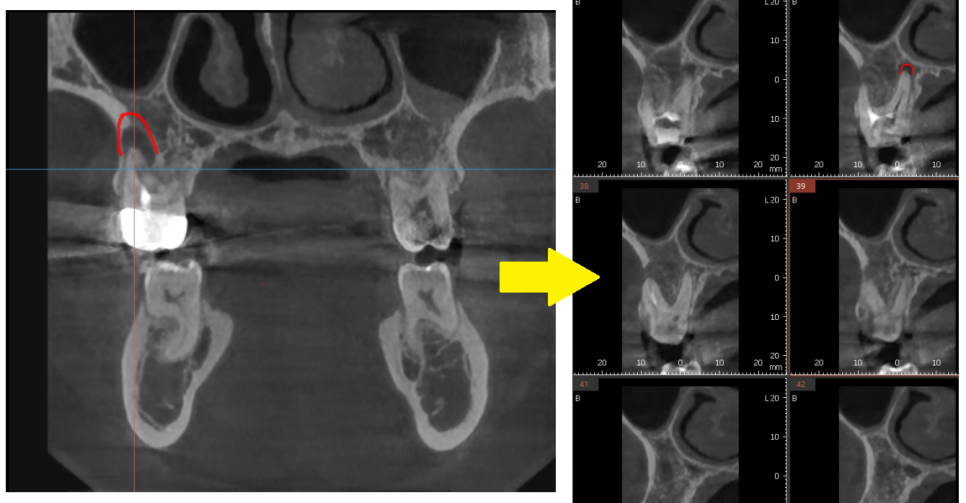

3D ct 등을 통해 정밀한 검사를 진행한 결과,

치아 뿌리 주변의 염증으로 한쪽 뼈를 녹였네요.

ct 상 한쪽 뼈만 녹아있는 상황이라

반대편 뼈에 기대해보면서

뿌리 절반 이상 염증들이

3달의 치료과정을 통해

손톱만큼 줄어들었습니다.

이제 뿌리 끝 까만 부분

거의 보이지 않습니다.

염증이 남아있으면 제대로 뼈가 차지 않는대요.

깨끗하게 염증이 없어졌기 때문에

까맣게 녹아 버린 뼈가

다시 하얗게 채워진 모습을 볼 수있네요~